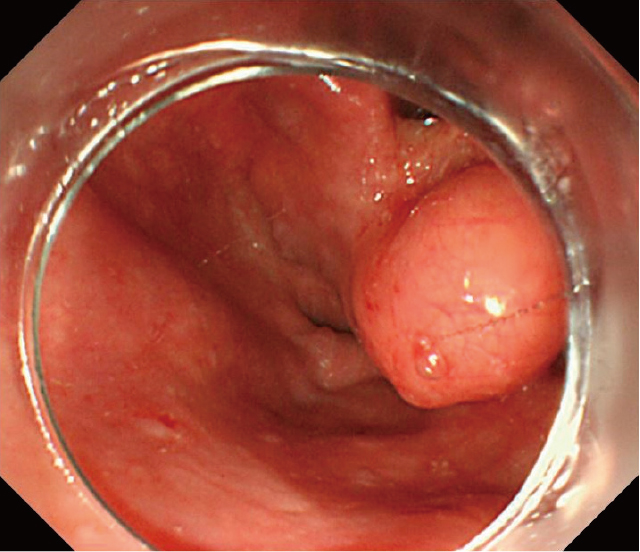

上部内視鏡検査:下咽頭右梨状陥凹に,表面平滑で黄色調の粘膜下腫瘍を認める(Figure 1).腫瘍は披裂喉頭蓋ひだに付着し,右側壁に連続しているように観察された(Figure 2).

下咽頭梨状陥凹に表面平滑,黄色調の粘膜下腫瘍様病変を認める.